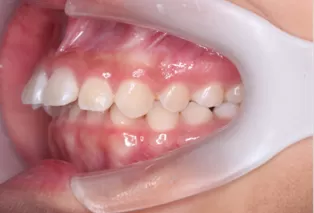

Photos intra-orales après traitement